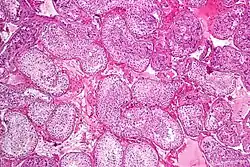

![]() Seminiferous tubule with maturing sperm. H&E stain. | |

Spermatogenesis is the process by which haploid spermatozoa develop from germ cells in the seminiferous tubules of the testicle. This process starts with the mitotic division of the stem cells located close to the basement membrane of the tubules.[1] These cells are called spermatogonial stem cells. The mitotic division of these produces two types of cells. Type A cells replenish the stem cells, and type B cells differentiate into primary spermatocytes. The primary spermatocyte divides meiotically (Meiosis I) into two secondary spermatocytes; each secondary spermatocyte divides into two equal haploid spermatids by Meiosis II. The spermatids are transformed into spermatozoa (sperm) by the process of spermiogenesis. These develop into mature spermatozoa, also known as sperm cells.[2] Thus, the primary spermatocyte gives rise to two cells, the secondary spermatocytes, and the two secondary spermatocytes by their subdivision produce four spermatozoa and four haploid cells.[3]

Spermatogenesis starts in the bottom part of seminiferous tubes and, progressively, cells go deeper into tubes and moving along it until mature spermatozoa reaches the lumen, where mature spermatozoa are deposited. The division happens asynchronically; if the tube is cut transversally one could observe different maturation states. A group of cells with different maturation states that are being generated at the same time is called a spermatogenic wave.[5]